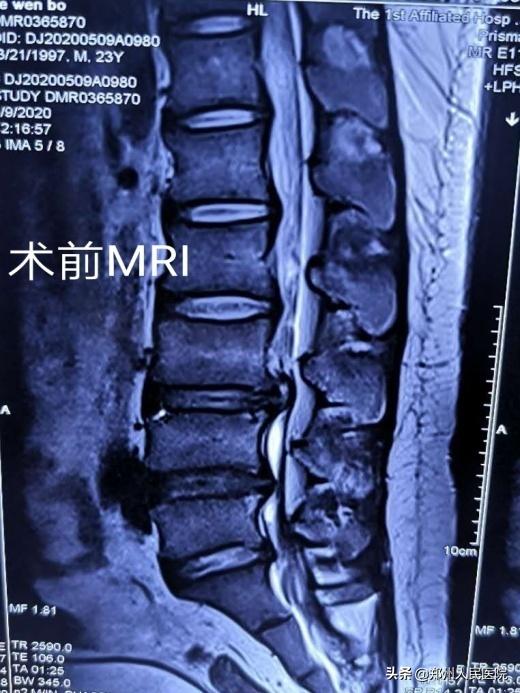

小葛立即去了省内的几家大医院看病,经过各项检查后,他被确诊存在“腰3/4椎间盘突出并髓核脱出,伴有椎管狭窄”。最让小葛纠结的是:每个医院给出的治疗方式不同,各种各样的治疗方式让小葛难以抉择。有的说可以保守治疗,有的说可以做微创手术,有的说必须进行开放手术效果才好。

田明波主任在听到小葛的情况后立即召开了全科室的病例讨论,针对患者的腰椎间盘椎管狭窄病情及患者年龄的特殊性进行反复论证,最终选择使用国内前沿的“单侧双通道UBE脊柱内镜技术”为小葛行手术治疗。

经过充分准备,对小葛实施的“单侧双通道UBE脊柱内镜术”如期举行。手术进行的十分顺利,经过一个半小时,手术成功。